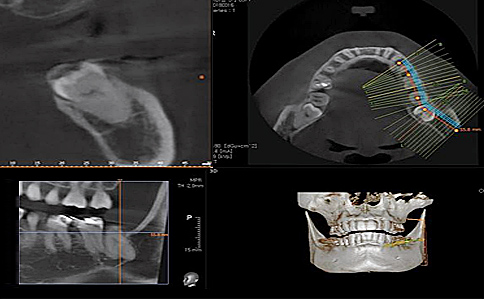

사랑니는 우리 입속에 가장 뒤에 난 어금니를 말하며, 전문용어로 설명해 드리면 제3대구치라고 하며 얼굴을 중심으로 좌우로 8번째 자리하고 있는 치아를 말합니다. 사랑니는 사춘기 이후에 자란다고 합니다. 사춘기에는 여러 가지 감정을 느끼게 되고 그 감정 중 하나가 사랑이라는 감정이지요. 그래서 이 치아를 사랑니라고 부른다고 합니다.

치과 치료를 하면 알 수 있는 것이 치아는 함부로 뽑지 않습니다. 정말 최대한 살려보고 그래도 안 되면 뽑아서 임플란트 등으로 빈자리를 채웁니다. 사랑니는 다른 치아들과 달리 발치를 해야 할 때도 있습니다. 잘 자란 사랑니는 특별한 문제를 일으키지 않아 뽑지 않아도 됩니다. 하지만 대부분의 사랑니는 말썽을 부립니다. 출혈, 염증, 통증 및 악취, 충치 들 여러 가지 문제를 일으킬 확률이 높기 때문에 뽑아야 합니다.